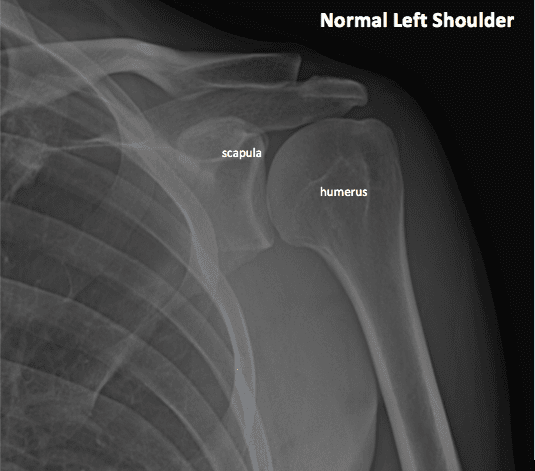

This bone, commonly known as the shoulder blade, serves as an attachment site for numerous muscles that support movement and stabilize the shoulder anatomy. The Scapula overlies the second to seventh ribs, and is encased by 17 muscles which provide control and stabilization against the ribcage. The bone also has a shallow socket on its lateral side, into which the head of the humerus fits to form the glenohumeral joint.

This is the upper arm bone, an important aspect of the shoulder’s anatomy because of the large range of movement that it permits. The head of the humerus is actually the ball of the ball and socket joint at the shoulder, and fits into the shallow socket (glenoid fossa) of the scapula.